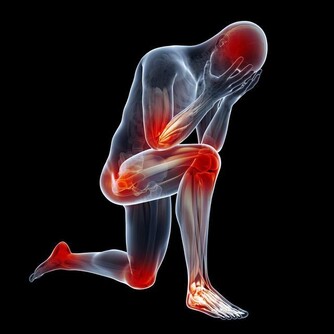

1、腿疼

外周動脈疾病最常見的表現就是跛行,病人時常會覺得腿疼、走路費勁。

有一些病人會感到雙腿疲勞、沉重,或者伴有灼痛。

這種疼痛會出現在下肢任何部位,休息後症狀減輕,如長距離行走會再次發作。

2、夜間抽筋

在睡眠中,病人常會腿抽筋,通常是在腳後跟、前腳或腳趾等部位。

把雙腳懸垂在床邊,在重力作用下讓血液流向雙腳,可以緩解疼痛。

5、麻木或虛弱無力

如果在靜止休息時,你的雙腳就有這種感覺,說明患上外周動脈疾病了。

6、小腿肌肉萎縮

有一些晚期病人可能注意到自己小腿的肌肉體積明顯縮小,

這是由於缺乏血液流動,導致肌肉纖維數量以及尺寸縮小。